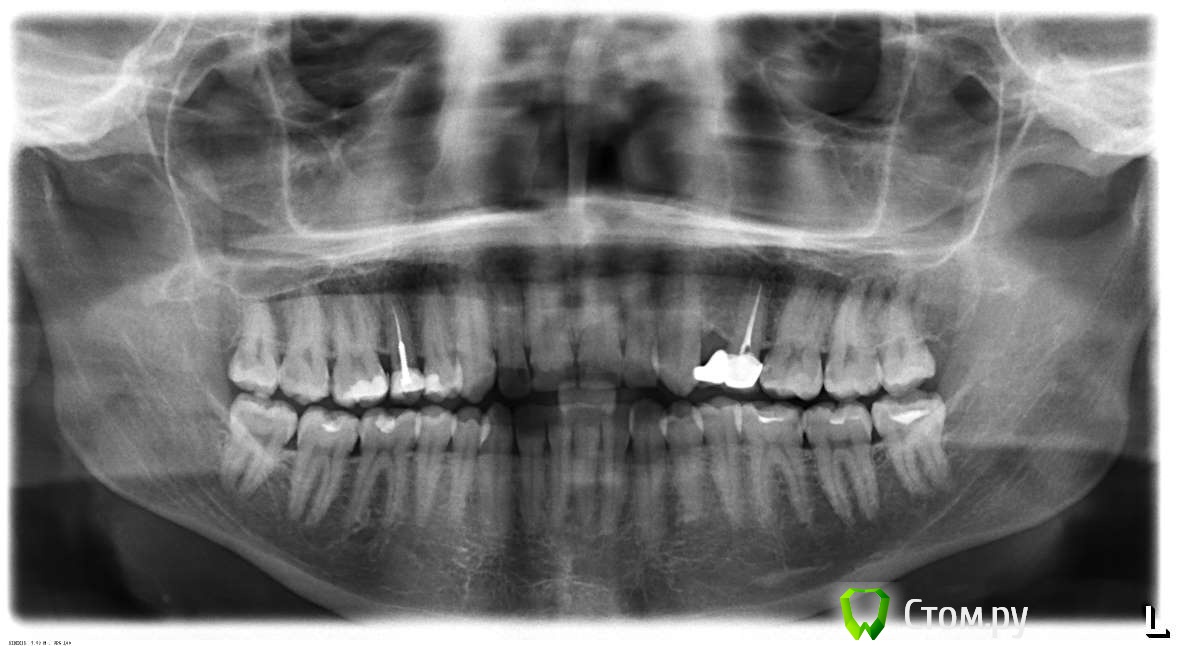

Усатый-Полосатый Опубликовано 10 июля, 2014 Поделиться Опубликовано 10 июля, 2014 Добрый день! 7 лет назад была сделана коронка, которая держится на одном зубе, а закрывает два зуба (на снимке справа): Сейчас стоматолог говорит, что ее нужно менять. Предлагает два варианта:1) поставить на пустое место имплант, а на соседний - поменять коронку на одинарную;2) поставить мост на три зуба, сточив клык. Но проблема в том, что десна сильно ушла вверх и истончилась на пустом зубе (фото): Можно ли при таком состоянии ставить имплант, не будет ли дополнительных проблем? Я так смотрю, что имплант будет под большим углом стоять и расстояние от металла до кости будет минимальным. Или, все же, лучше обычный мост поставить? Ссылка на комментарий

Усатый-Полосатый Опубликовано 11 июля, 2014 Автор Поделиться Опубликовано 11 июля, 2014 Еще такой вопрос. Есть ли показания к установки коронки на зуб с противоположной стороны, где стоит штифт? Верхний ряд четвертый слева на снимке. Шрифт ставили тоже 6 - 7 лет назад. Ссылка на комментарий

red_butler Опубликовано 11 июля, 2014 Поделиться Опубликовано 11 июля, 2014 Еще такой вопрос. Есть ли показания к установки коронки на зуб с противоположной стороны, где стоит штифт? Верхний ряд четвертый слева на снимке. Шрифт ставили тоже 6 - 7 лет назад. Да, 1.5 зуб нужно протезировать 1 Ссылка на комментарий

Усатый-Полосатый Опубликовано 11 июля, 2014 Автор Поделиться Опубликовано 11 июля, 2014 Понятно, спасибо. А, вообще, как состояние зубов и десен для 30 лет по снимку? Не слишком все плохо? Ссылка на комментарий

red_butler Опубликовано 11 июля, 2014 Поделиться Опубликовано 11 июля, 2014 Понятно, спасибо. А, вообще, как состояние зубов и десен для 30 лет по снимку? Не слишком все плохо?все, не плохо 1 Ссылка на комментарий